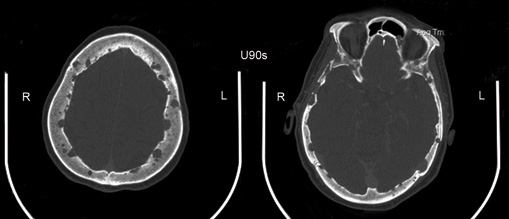

Paciente de sexo femenino de 62 años de edad, mexicana, que se presenta al servicio de urgencias por alteración del estado de alerta, desorientación, somnolencia, a su ingreso con fiebre de hasta 40 °C, TA 90/mm/Hg, FC 120x’, FR 20x’, alucinaciones visuales y lenguaje incoherente, rigidez de nuca y signos de Brudzinski y Kernig positivos, con disminución simétrica de la fuerza en las cuatro extremidades 3/5, sin focalización, al examen de fondo de ojo no se identificó papiledema. Su historia médica previa incluye historia de histerectomía por miomatosis uterina de grandes elementos, refirió lumbalgia desde 2 semanas previas, sin limitación funcional y sin haber recibido tratamiento, no ingesta de medicamentos, drogas o herbolaria y sin otros patológicos relevantes. Se identificó leucocitosis por neutrofilia, se obtiene líquido cefalorraquídeo (LCR) y se identifica turbio, con hipoglucorraquia de 13 mg/dl (rango 40-70), hiperproteinorraquia de 3200 mg/dl (rango 20-45), pleocitosis de predominio polimorfonuclear 85 % y presencia de cocos Gram positivos. Se hace el diagnóstico de meningitis bacteriana y se inicia tratamiento con ceftriaxona, vancomicina y ampicilina, no desarrolló crecimiento bacteriano en cultivo. La paciente presentó resolución de los signos meníngeos, sin embargo, al volver a estado consciente aqueja de lumbalgia intensa, dolor en miembros pélvicos y paraplejía. Se identifica en radiografía simple y tomografía la presencia de fractura por compresión a nivel de T12 y L3 y lesiones líticas en cuerpos vertebrales dorsales y lumbares, cráneo, húmeros, sacro y pelvis (figuras 1 a 3) fue valorada por neurocirugía considerándose no candidata a descompresión quirúrgica.